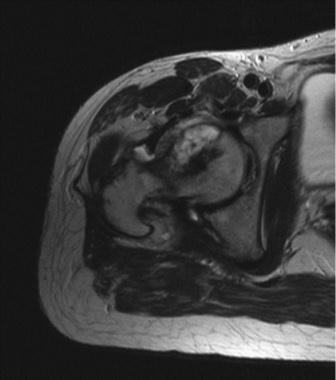

Eine 31-jährige Patientin klagte über rechtsseitige Schmerzen im Bereich der Leiste und des Hüftgelenkes mit Ausstrahlung in das Bein. Die Symptomatik bestand seit 18 Monaten und hatte zuletzt an Intensität zugenommen. Klinisch zeigte sich eine endgradige schmerzhafte Bewegungseinschränkung des rechten Hüftgelenkes. Die konventionelle Röntgenuntersuchung ergab eine osteolytische Raumforderung im ventralen Anteil des rechten Hüftkopfes und Schenkelhalses, die partiell von einem Sklerosesaum begrenzt war. Im MRT zeigte sich eine auf den ventralen Hüftkopf und Schenkelhals begrenzte Raumforderung, deren Dignität nicht sicher zu beurteilen war (Abb. 1). Szintigraphisch ergab sich eine deutliche Mehranreicherung im Bereich des rechten proximalen Femur bei sonst unauffälligem Befund. Somit war ein Malignom nicht auszuschließen. CTs von Thorax und Abdomen zeigten keine weiteren Tumormanifestationen oder Metastasen. Eine CT-geführte Stanzbiopsie des Tumors ergab ein osteoblastisches Osteosarkom.